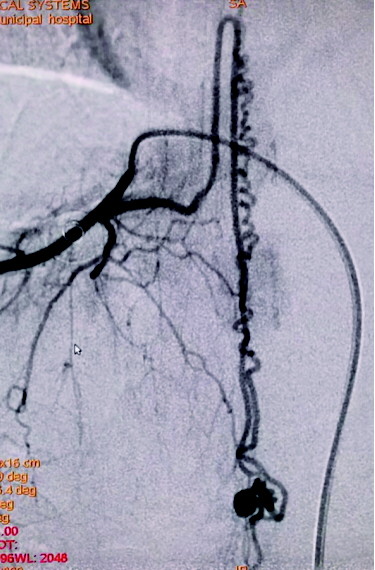

图A为术前造影的正位图像,主供血为脊髓前动脉,引流静脉的起始部形成一个静脉球,远端呈迂曲状;图B为微导管到位后的超选造影,脊髓前动脉不显影(已越过);图C为栓塞结束后的造影,主供血的血流明显瘀滞,瘘口闭塞,下方的脊髓前动脉仍显影。